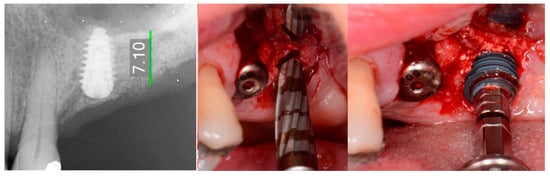

The patient returned at 10-weeks implant and graft placement and the soft tissue over the posterior quadrant was noted to be healed with no inflammation present (Figure 10 left). Following local anesthetic administration a full thickness flap was elevated and the previously grafted 2nd molar crestal area was filled with immature host bone (Figure 10 right). A radiograph was obtained, which noted a crestal height of 7.1 mm present (Figure 11 left). The 2nd molar site was prepared in a similar fashion as previously detailed, utilizing Densah burs to osseodensify the area and accomplish a crestal sinus augmentation and a 5 × 8.5 mm Anyridge implant was placed (Figure 11 middle and right). An impression of the 1st molar implant was obtained to initiate its restoration while the 2nd molar implant was integrating. A healing abutment was placed on the implant at the 1st molar and a cover screw on the 2nd molar implant and a radiograph obtained to document the clinical result to date (Figure 12).

Figure 10.

The keratinized gingiva at 10 weeks post-surgery (left) and following flap of the site demonstrating conversion of the osseous graft at the 2nd molar site that will allow implant placement at that site (right).

Figure 11.

Radiograph demonstrating sufficient height of the ridge to allow primary stability of an implant placed at the 2nd molar with a crestal sinus augmentation at 10 weeks of graft healing (left), site preparation for the crestal sinus augmentation (middle) and implant placement into the site (right). Green line is the measurement of the height of the bone at that point between the crest and the sinus floor.